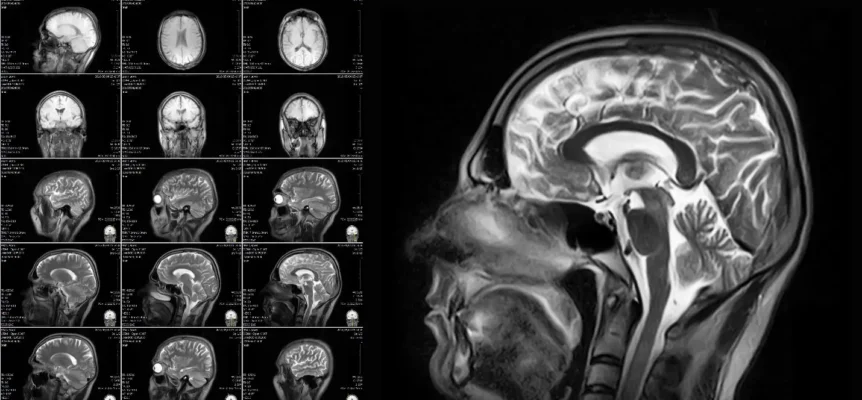

Drug Delivery System Imaging Technology options include MRI, CT, and Ultrasound. This article highlights advantages and disadvantages for each technology in guiding drug delivery.